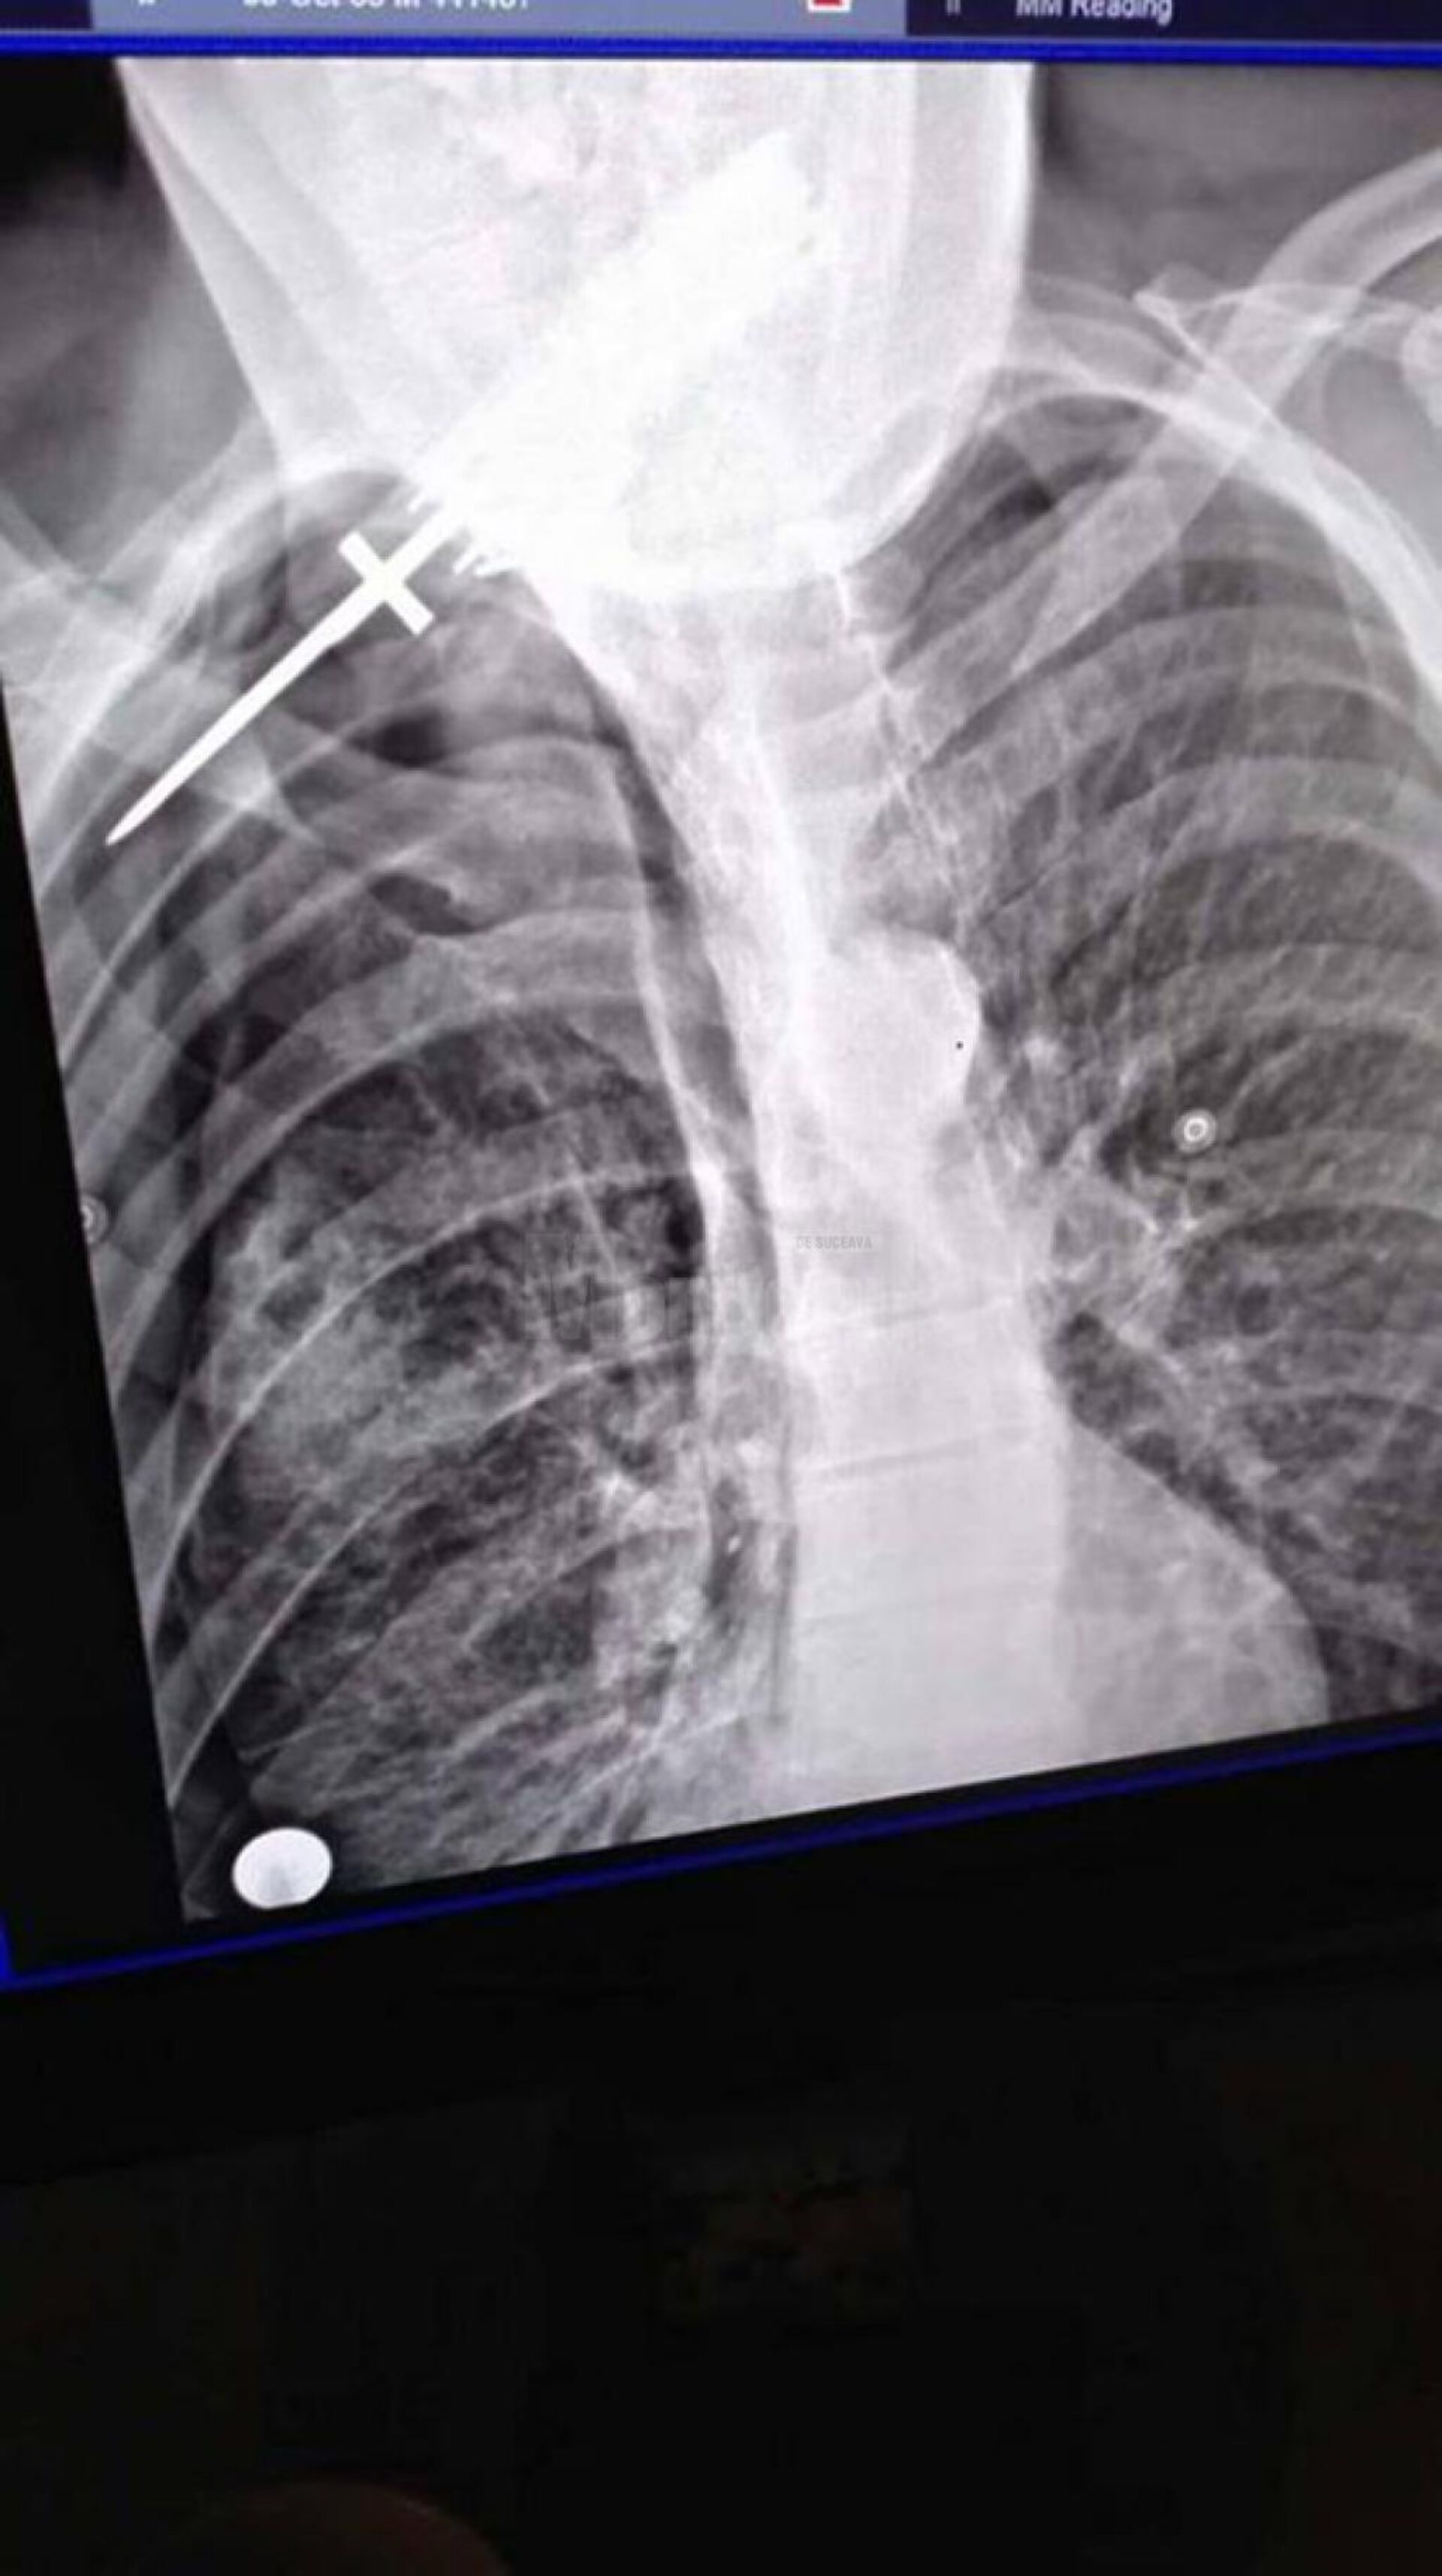

Pe 11 iunie, în jurul orei 23.45, Postul de Poliție Arbore a fost sesizat prin 112 de o femeie, Luminița C., din Clit, că Neculai F., de 53 de ani, concubinul ei, a fost înjunghiat. Bărbatul a fost transportat la Spitalul Județean Suceava, unde a fost diagnosticat cu plagă înjunghiată hemitorace dorsală, cu retenție de corp străin – cuțit.

Medicii de la Spitalul Județean Suceava au constatat că pacientul era stabil hemodinamic și respirator. El a fost operat de urgență, pentru pneumotorax traumatic și pentru extragerea corpului străin.